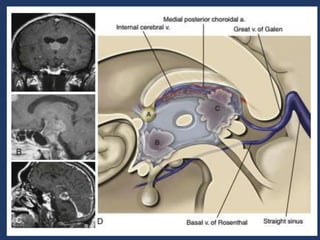

• between the tela choroidea, is a space, the velum

interpositum, through which the inernal cerebral

veins and medial posterior choroidal arteries course

• the ICVs start at the posterior edge of the foramen of

Monro and run posteriorly to exit the velum

interpositum just above the pineal body.

• the third ventricular choroid plexus is attached to the

roof by tela thoroidea